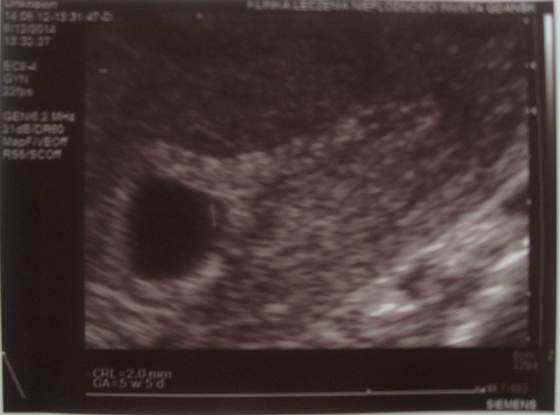

Ja tak znowu na szybko bo wpadłam na chwilę do pracy a tu mam stacjonarnego kompa więc mi łatwiej. Opis z wizyty: "W jamie macicy obecny jeden pęcherzyk ciążowy wielkości odpowiadający wiekowi ciąży (GS-13,3 mm), echo płodu: CRL = 2,0 mm, ASP - TAK, Pęcherzyk żółtkowy - TAK, YS - 3,6 mm, Doczesna - OK, JP i JL prawidłowe." Zmniejszył mi lutkę do 3 x 150 dowcipnie i 3 x 150 podjęzykowo, reszta leków bez zmian. Kolejna wizyta 19.08.2014. już u niego w gabinecie w Elblągu o godzinie 19:30 :-)

Fotka dla cioteczek